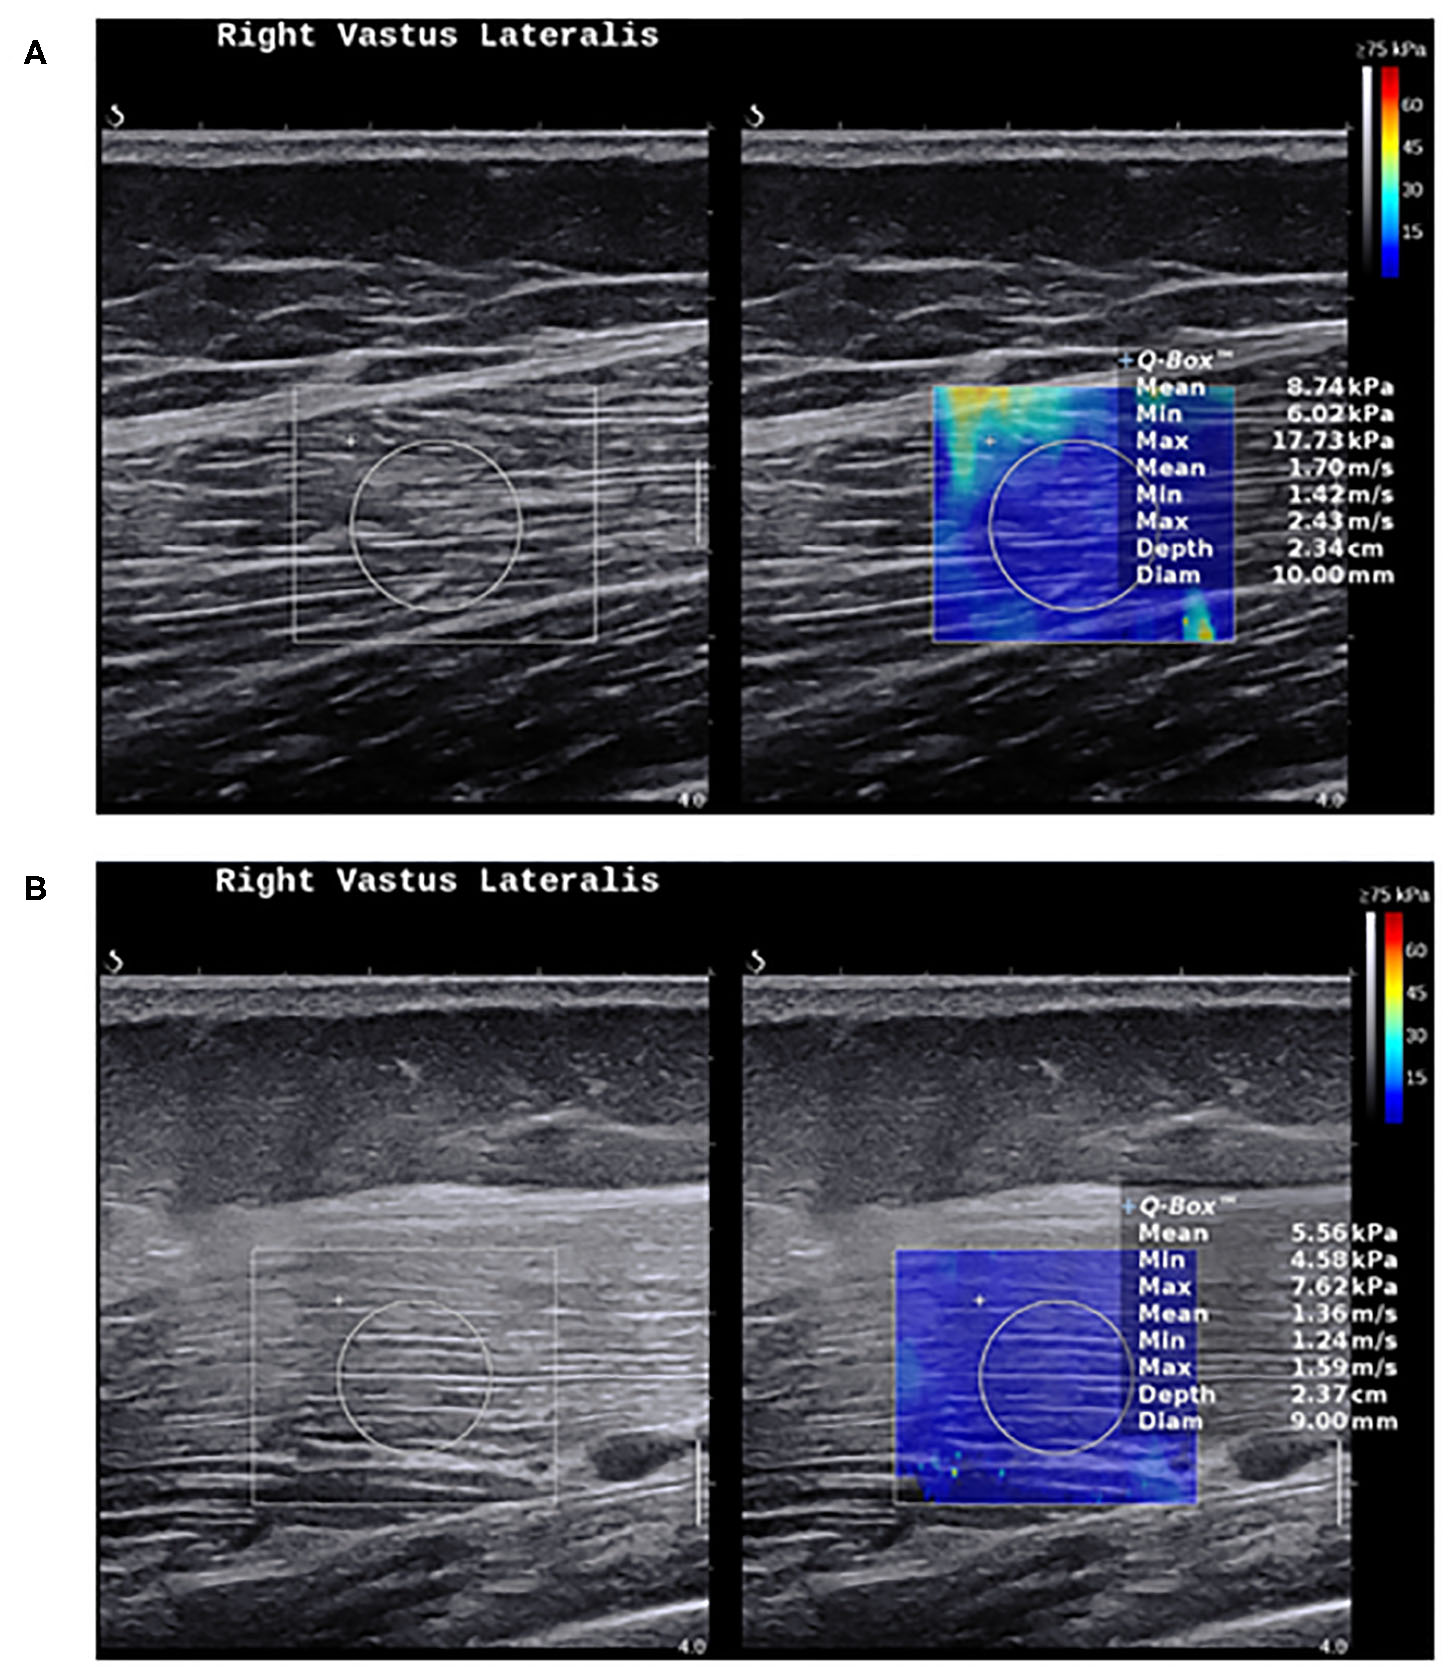

Nevertheless, the current evidence suggests that SWE shows less muscle stiffness in myositis compared to healthy individuals (Figure 3), and can distinguish myositis from normal muscles (86). The loss of muscle stiffness in myositis patients was also observed using magnetic resonance elastography (87). SWE measurements also correlate with muscle strength and MRI grades of edema and atrophy (86, 88). All of these findings appear to only manifest when the muscles are under no passive or active loading.

Figure 3. Shear wave elastography in healthy muscles and myositis. (A) Shows a normal muscle stiffness (8.7 kPa) in a 50-year-old healthy female person. (B) Shows a low muscle stiffness (5.5 kPa) in a 49-year-old male with active polymyositis.